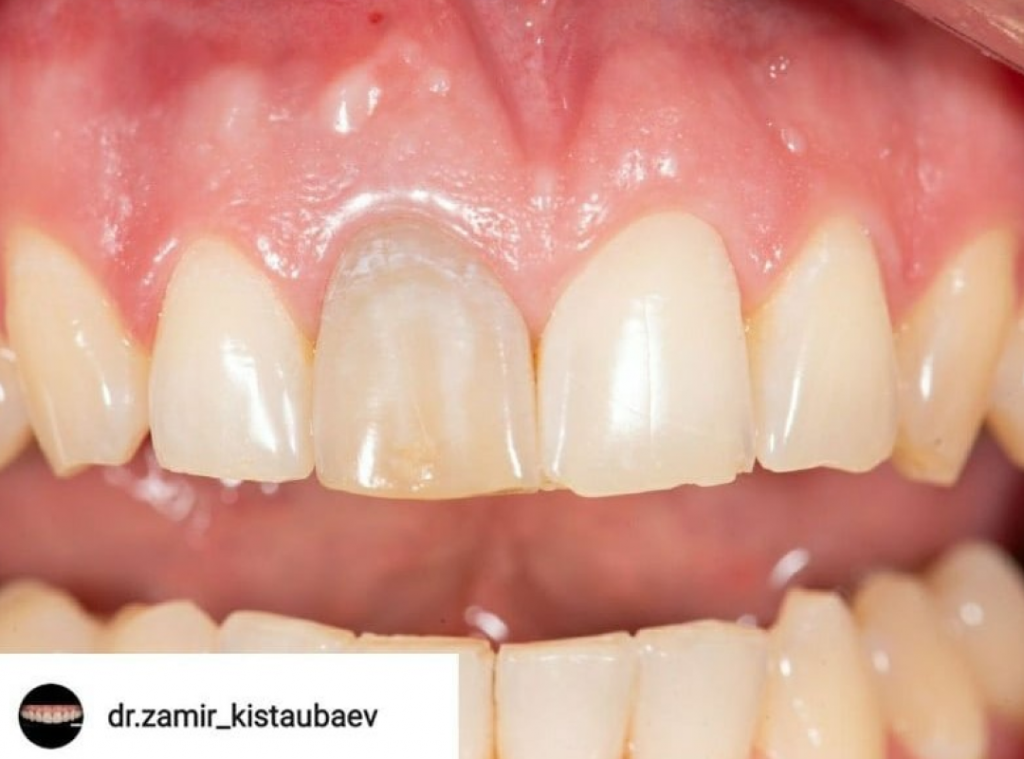

На КТ была обнаружена трещина корня, не позволяющая вылечить зуб. Было принято решение об удалении зуба с одномоментной имплантацией. Коронковую часть временного зуба восстановили из родного зуба пациента, предварительно отреставрировав его перед установкой.

Срок ношения временной конструкции 4 месяца.